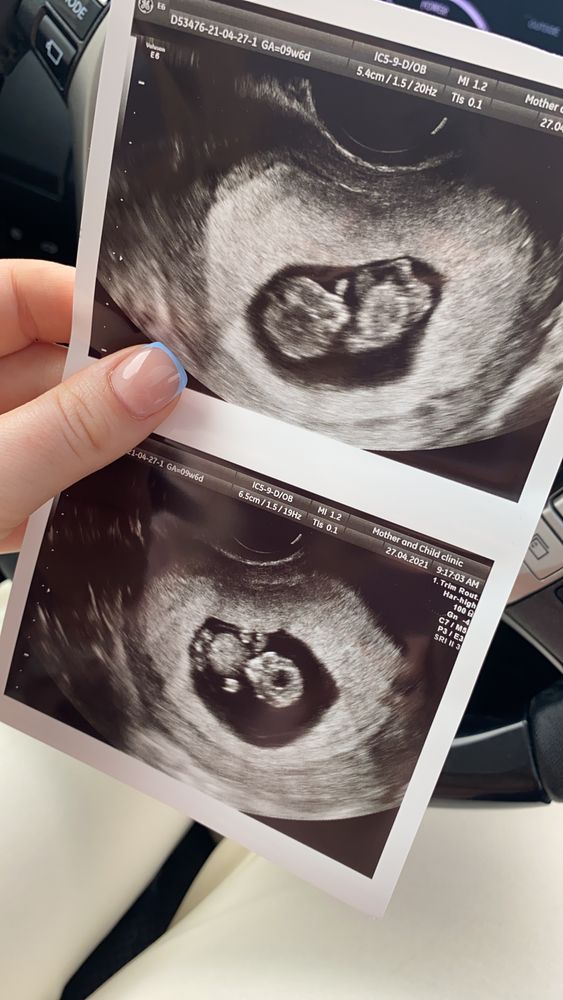

Сходила на УЗИ для контроля сердцебиения 💓.

Какого было мое удивление, что во втором плодном Яйце, которое врач ЖК назвал «замершим и неразвивающимся» нашли эмбриончика и уже с сердцебиением. 😭

эмоции не передать словами. Первое ЭКО, первое крио, и сразу двойня ❤️👏🏼